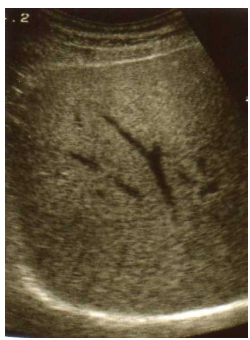

22 14 歲女性,肺活量預測值為 1.87L,流量-容積曲線(flow-volume curve)如圖所示,此人的肺功能診 斷最可能為: (A)正常 (B)阻塞型通氣障礙(C)侷限型通氣障礙(D)混合型通氣障礙